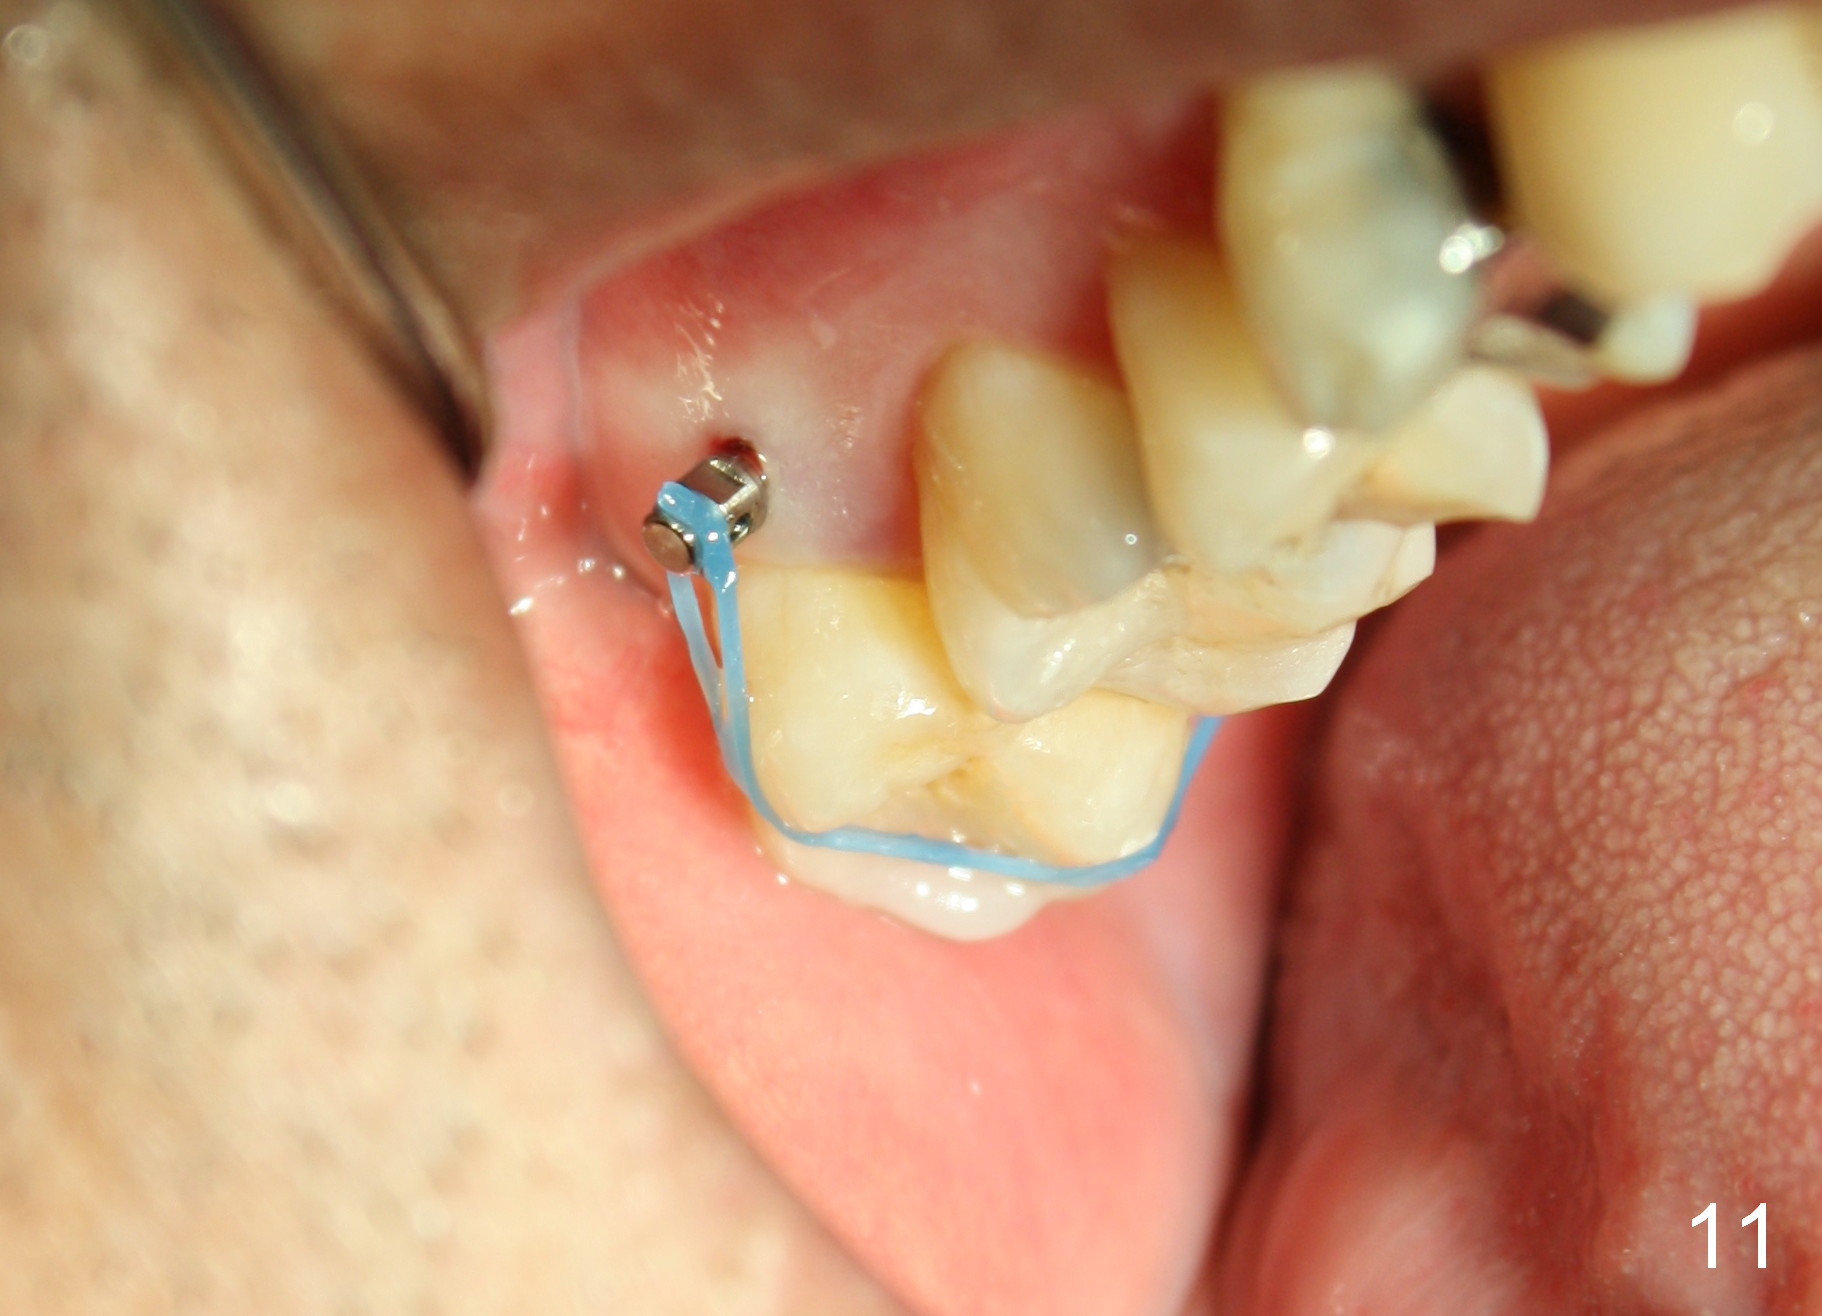

The wound heals uneventfully (Fig.8,9: taken 3 months postop). When an abutment is placed, there is no clearance for a crown. Two mini-implants are placed for the tooth #2 intrusion (Fig.10,11). Four months later, segmental orthodontic appliance is added because of lack of result of intrusion and buccoversion of the tooth #2 (Fig.12). Two months later, all of orthodontic treatment is terminated at the request of the patient. After heavy reduction of the tooth #2, a crown is cemented. Fig.13 (panoramic X-ray) is taken 11 months post cementation. There is no bone loss nearly 3 years post cementation (Fig.14).